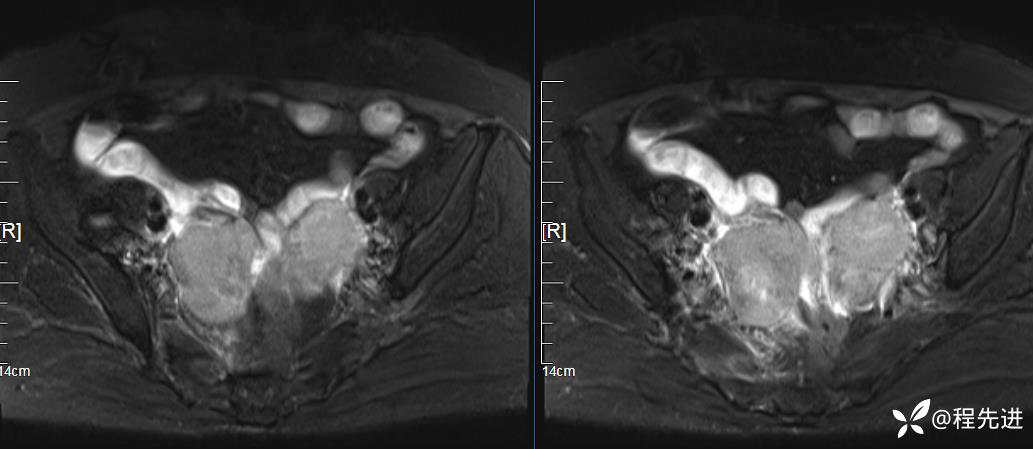

DWI、ADC:

患者性别:女

患者年龄:76岁

简要病史:下腹痛伴发热半月余

实验室检查:肿瘤指标均正常